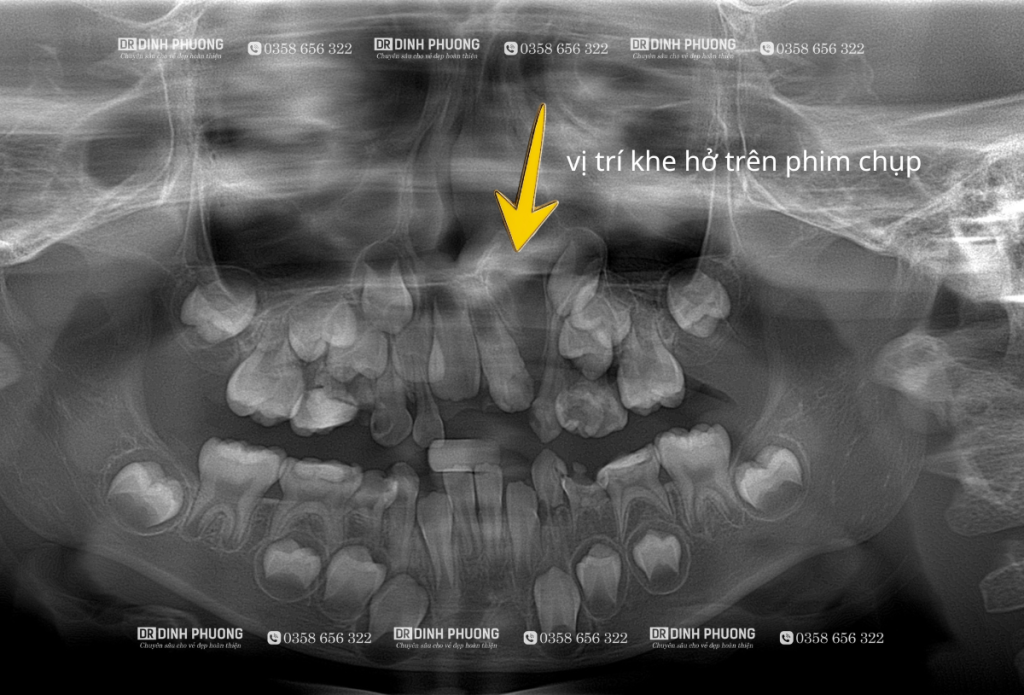

Phim chụp panorama và phim chụp CT Cone beam.

Hình ảnh cho thấy tồn tại khe hở cung răng và vị trí của mầm răng đang di chuyển từ vị trí sàn ổ mắt xuống khe hở, đây là thời điểm thích hợp để tiến hành ghép xương.